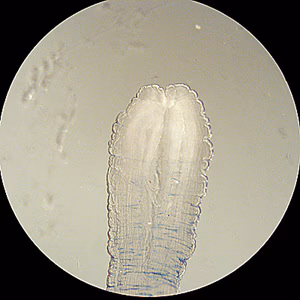

Spargana removed from tissue

Diagnosis is usually made by the recovery of a sparganum from infected tissue. The presence of a sparganum is diagnostic and identification to the species level is usually not warranted. However, the best way to identify the species is to infect an appropriate definitive host with a living sparganum and identify the adult after maturation.